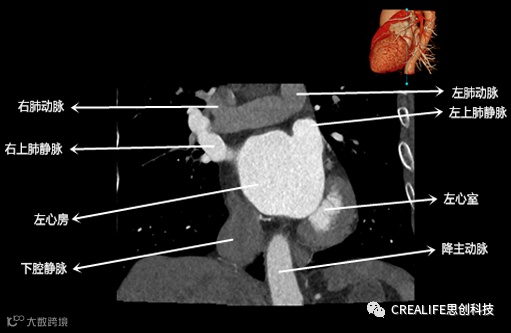

今天,跟大家分享心脏影像的经典层面——冠状位。通过冠状位的影像,我们可以从正位观察到心脏结构,看到主动脉的纵向剖面及冠窦交界处的心脏形态等多方位的心脏结构。现在,就让我们率先一睹“冠状位”的奇妙风采吧!

毋庸置疑,影像解剖学可为医师提供优良的诊断依据,包括瓣膜钙化程度、主动脉瓣环直径、主动脉窦直径及高度、冠状动脉开口高度、入径血管直径等关键数据,以此,为术前提供更全面的评估指标。